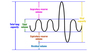

inhalation

diaphragm + external intercostal muscles

diaphragm flattens, chest expands

increasing intrapleural volume, lowering pressure

air comes in

negative-pressure breathing

mechanism of breathing whereby pressure differential ultimately expands the lungs, decreasing pressure

causes air to come into the lungs from the environment

exhalation

relaxation of muscles

diaphragm raises back up, decreasing volume, increasing pressure

air leaves lungs